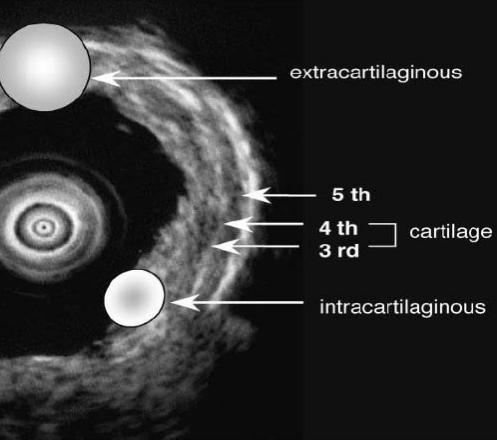

早期中央 型 肺癌侵犯深度的界定

原位癌就在粘膜层,微侵袭癌在肌肉层和软骨内膜,超过软骨内膜就是侵袭了。除了使用超声观察,还可以使用OCT,OCT可以提供比超声更高分辨率的中央气道壁结构图像,尤其是软骨及软骨内膜情况,但是看的范围浅。

超声探头用于早期癌症分期,指导治疗

治疗原则:1. 肿瘤侵犯深度在软骨内膜可采用局部治疗:光动力,后装放疗,氩气,冷冻,电凝;2. 肿瘤侵犯深度超过软骨内膜应手术治疗。